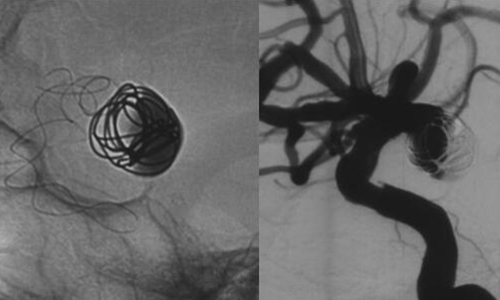

术中,张琪主任及脑血管病团队在刘建民教授指导下将Tubridge血管重建装置专用支架导管T-track到位,在动脉瘤内的一枚弹簧圈保护下,植入Tubridge5.0mm*35mm支架。准确定位后,锚定支架头端,缓慢推送支架的同时控制支架张力,顺利释放支架。为进一步确保Tubridge血管重建装置完美贴壁,上J型导丝支架内“按摩”。多角度确认支架已完全充分贴壁。将病变血管的腔内重建后,正侧位造影示动脉瘤内造影剂明显滞留,载瘤动脉通畅,血流导向作用显著,分支血管均未受影响,手术取得良好效果。

▲支架完全释放后造影,动脉瘤显影变小,造影剂明显滞留